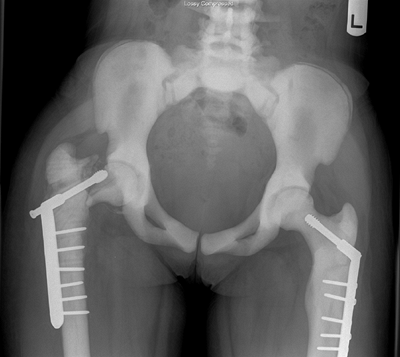

![]() |

Figure 7.12 Osteogenesis imperfecta (OI). A: An extensible rod is used in this 7-year-old girl with severe OI. B: The rod has grown with the femur over a 3-year period.